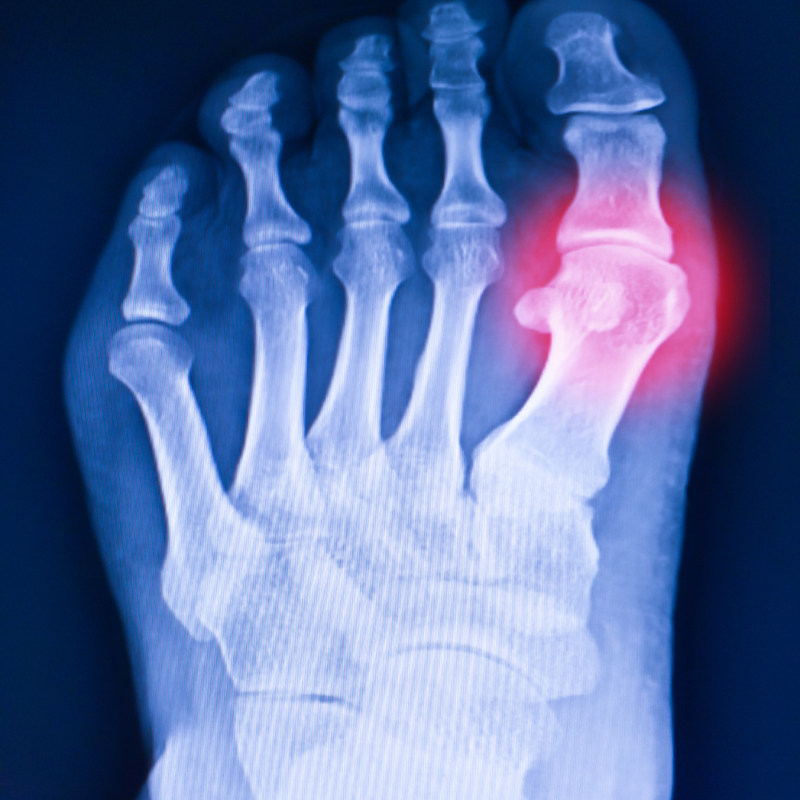

Sesamoiditis is an inflammation type injury that affects the tendons surrounding the sesamoid bones. The sesamoid bones are two small pea shaped bones that sit under the big toe joint.

The sesamoid bones and surrounding tendons function as a kind of pulley system to assist toe flexion and propel the body forward from the toes when you take a step.

In severe cases, a sesamoid fracture may occur in the medial sesamoid (or tibial sesamoid) bone. Medical experts must take care to diagnose fractures correctly because some people naturally have a bipartite medial sesamoid that may give the appearance of a fracture.